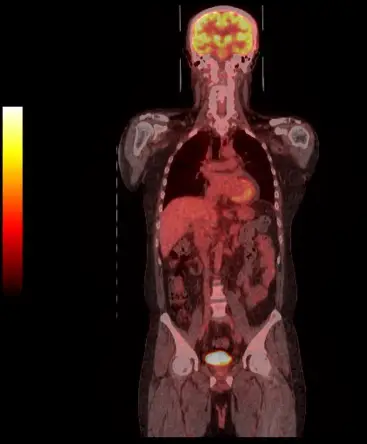

下圖為臨床判讀正子影像工作站的呈現方式,此影像以何種方式呈現?

- 切面方向(Plane):影像呈現從頭部到骨盆腔的正面全貌,屬於將人體分為前後兩半的冠狀切面(Coronal plane)。

- 影像模式(Modality):影像背景為高解析度的灰階解剖構造(如骨骼、肺部、腸胃道等),這是由電腦斷層(CT)提供的;而疊加在上面呈現紅黃橘等彩色的區域,代表放射性藥物(如 18F-FDG)的局部高攝取量(如大腦、心肌、肝臟、膀胱),這是由正子造影(PET)提供的代謝資訊。

- 呈現方式(Presentation):將上述的灰階 CT 影像與彩色 PET 影像疊加在一起,即為融合影像(Fused imaging)。